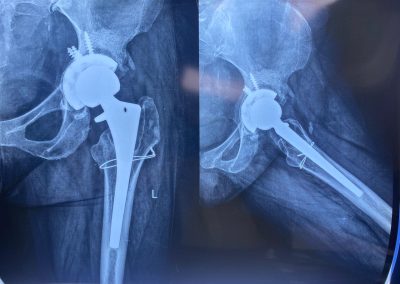

بعد اجراء جراحة تغيير للمفصل مع ترقيع عظمي من بنك العظام

تبين الأشعات ملء الفجوات بالترقيع العظمي.